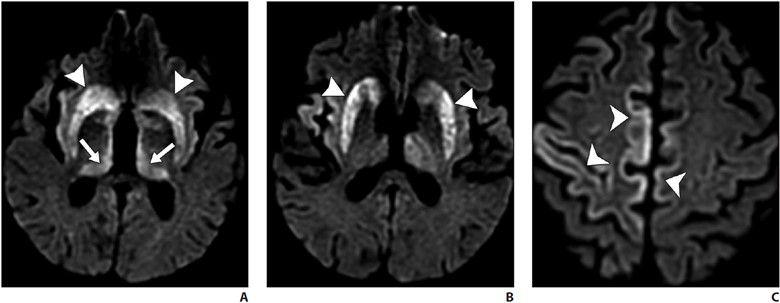

A fatal prion disease, CJD presents with rapidly progressive dementia, along with myoclonus, pyramidal, extrapyramidal, and cerebellar signs. CJD is mostly sporadic, but it can be familial, infectious (variant CJD), or iatrogenic. There is spongiform degeneration and gliosis. The MRI sequence with the highest sensitivity and specificity is DWI, which shows the characteristic imaging finding of hyperintensity of the basal ganglia, thalami, and the cortical regions [38, 39] (Fig. 8).

A–C, Axial diffusion-weighted MR images of patient presenting with rapidly progressive cognitive decline show signal abnormality in bilateral corpus striatum (arrowheads, A and B), thalamic pulvinar (arrows, A) and scattered cortical gyriform reduced diffusion (arrowheads, C). Hockey-stick configuration of dorsomedial and pulvinar involvement is commonly described with Creutzfeldt-Jakob disease.

Symmetric involvement of the posterior thalami (pulvinar sign) and the dorsomedial nuclei (hockey-stick sign) is common in variant CJD but can also be seen in sporadic CJD. Bilateral but asymmetric involvement of the cortical areas is seen [38, 39]. Enhancement is uncommon. Definitive diagnosis may require brain biopsy. Death ensues in a few months.